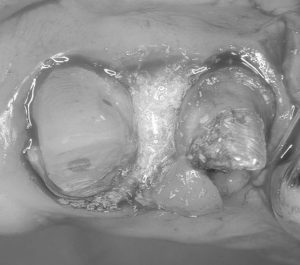

ピエゾサージェリーという超音波機器を今年導入してから、歯周外科がそれまでよりもスピーディーに行えるようになりました。前歯の審美障害と歯周治療希望で来院された患者さんです。犬歯の下がった歯肉は完全でなくてもある程度カバーできればいいというご希望だったので歯肉移植はしませんでした。その労力が省けた分、歯周組織再生療法を同時に行うことができました。術式も今年の3月に学んだばかりの方法で行いました。術後まだ10日なので歯肉の形は落ち着いていませんが、数か月待ってブリッジの型取りに行ければと思います。いつも準備やアシストをしてくれるスタッフには本当に感謝です。とても一人ではできないと常々思います。

根面被覆と再生療法を同時に